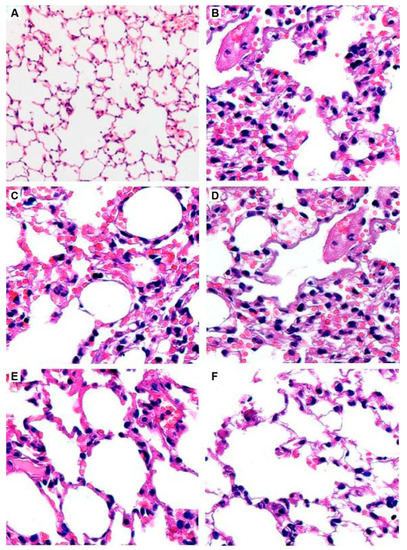

In order to develop nebulizer formulations of antifungal agents, commercially available VRZ IV formulation containing 100 mg/mL sulfobutyl ether-β-cyclodextrin sodium was aerosolized for nebulization in 2009. According to the results of in vivo study in Aspergillus fumigatus-infected outbred ICR mice treatment with aerosolized VRZ has significant survival advantages (92%) as compared to treatment with AmB (25%). This improved survival rate in the infected mice might be attributed to the reductions in the extent of invasive PA with the administration of aerosolized VRZ. Besides, the aerosolized formulation was also well tolerated with the absence of lung injury or inflammatory changes based on histological findings in uninfected mice [68].